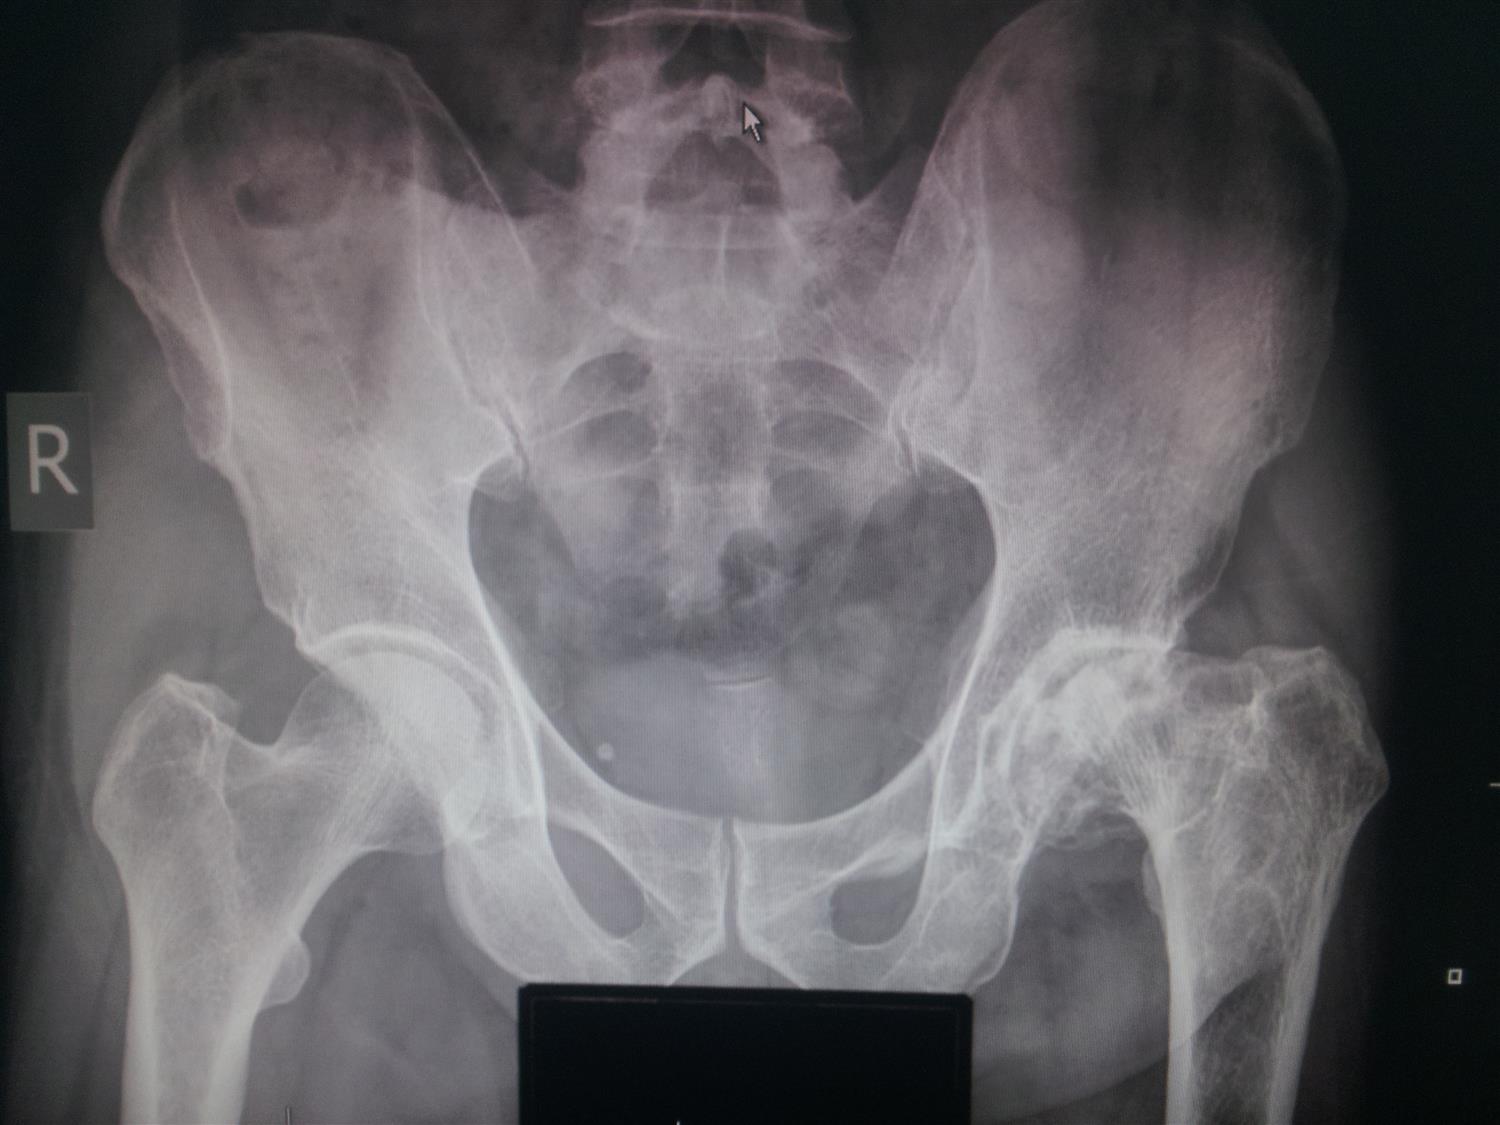

Hip Osteoarthritis Recon Orthobullets Hip Arthritis Orthobullets hip osteoarthritis is degenerative disease of the hip joint that causes progressive loss of articular. osteoarthritis (oa) of the hip is the most common form of joint disorder of the hip, affecting primarily the articular cartilage of the hip joint. orthobullets review topics included. hip pain is often localized to one of three locations: A degenerative. Hip Arthritis Orthobullets.

Bilateral protrusio acetabuli of the hip BMJ Case Reports Hip Arthritis Orthobullets hip pain is often localized to one of three locations: location and technique. recent joint surgery or cellulitis overlying a prosthetic hip or knee were the only findings on history or. hip osteoarthritis is degenerative disease of the hip joint that causes progressive loss of articular. hip arthrodesis is the fusion of the hip joint. Hip Arthritis Orthobullets.